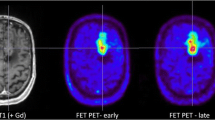

Example of two patients with concordant imaging results (A) and incremental diagnostic value of [18F]FET-PET (B). A Example of a patient (#10) with an anaplastic astrocytoma WHO grade III who was treated with combined radiochemotherapy prior to PET. Axial T2WI and T1WI + CE depict the tumor in the left thalamus and insular region (red arrows); axial PET shows high uptake of [18F] FET in these regions (white arrows). Both MRI and PET identified correctly the tumor recurrence. B Example of a patient (#19) with a pilocytic astrocytoma who was treated with surgery and chemotherapy prior to PET. Axial T2WI and T1WI + CE show cystic as well as contrast enhancing lesions next to the surgical cavity consistent with both unspecific changes and tumor recurrence (red asterisk); in contrast, axial PET demonstrates focal high uptake of [18F]FET (white asterisk)